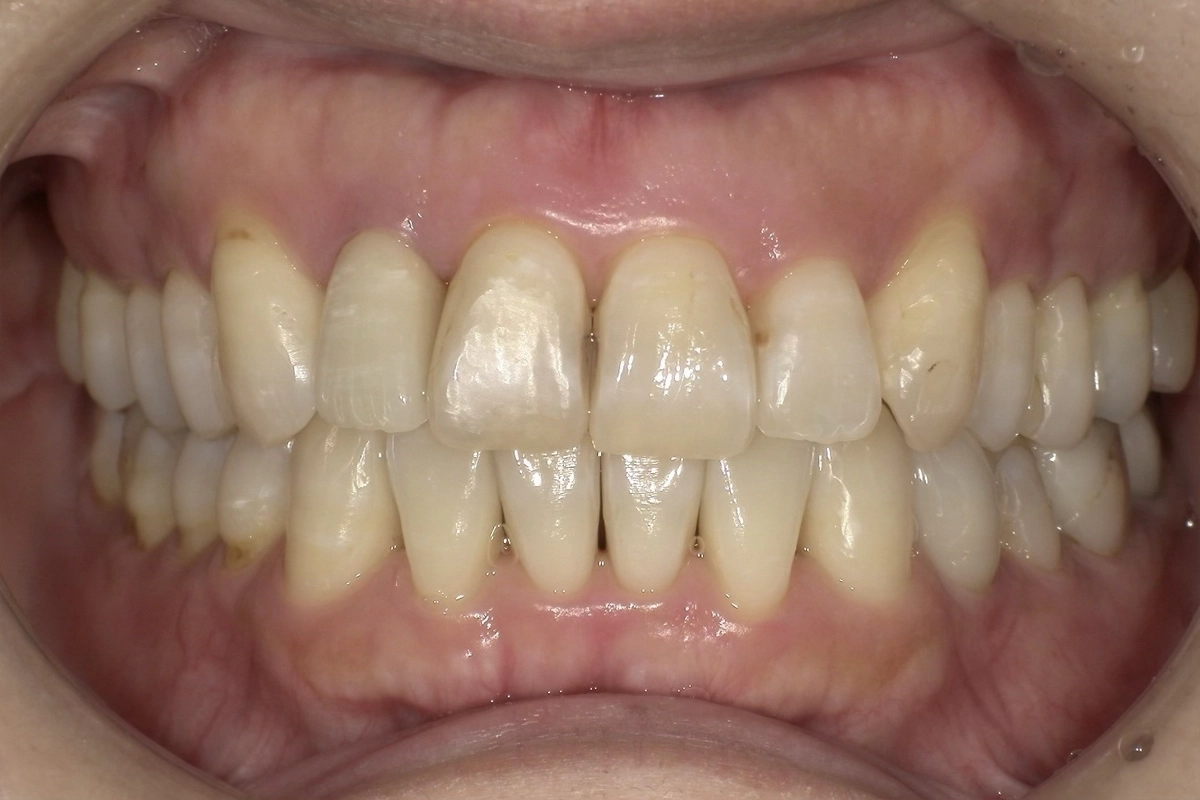

この方は「前歯のガタガタが気になる」というご相談で来院されました。

特に下の前歯は歯同士が重なり合い、一部の歯が前後にずれて不規則に並んでいる状態でした。

上の前歯にも軽度の乱れがあり、左右の側切歯から犬歯にかけて歯列のアーチが崩れていました。

正面から見たときに歯並びの不揃いが目立ちやすく、口元の印象に影響を与えていました。

重なり合っていた上下の前歯がきれいに配列され、滑らかなアーチを描く歯並びになりました

正面から見たときの口元の印象が大きく変わり、患者様にも喜んでいただけました。